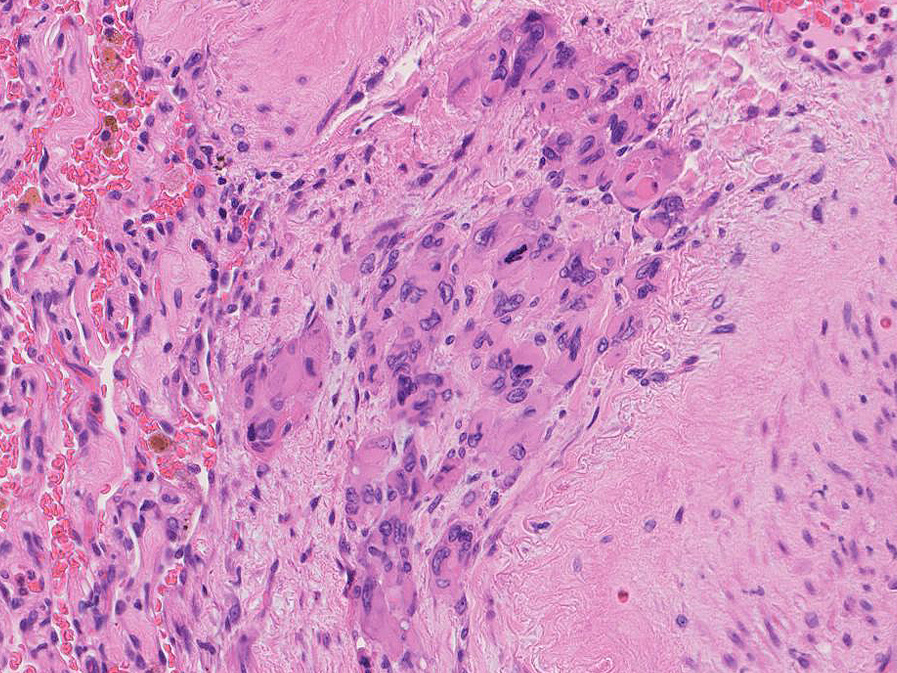

直径5-6mmの, 中央に弾性線維をふくむfibrous noduleがあり, 腫瘍細胞は結節の辺縁部に沿って認められる。

hyperchromaticな類円ないし多角の核で好酸性の広めの細胞質をもつ上皮様細胞が増殖している。右図では血管内を占拠するように腫瘍細胞が認められる。

右図:多型細胞や異型細胞が出現。核分裂像も異常に見える。